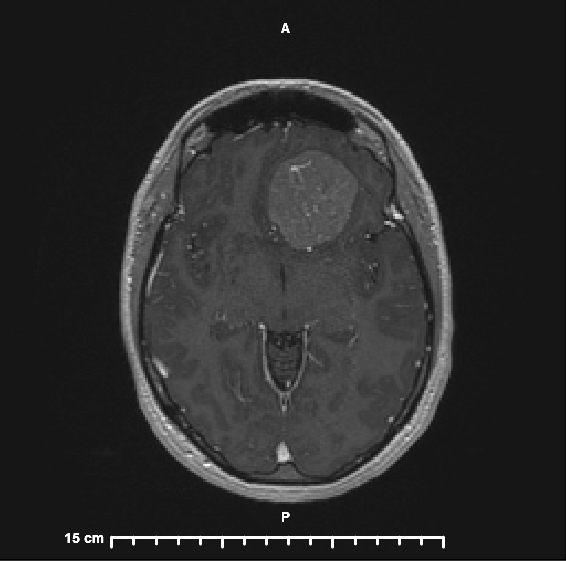

I have a brain tumor.

That is by far the strangest sentence I’ve ever spoken or typed. The doctors are 99% sure that it is a Benign Meningioma. I will be undergoing surgery to have it removed on December 13. I am still wrapping my head around this (no pun intended) but my overall feeling about it is that I knew there was something wrong; we figured out what it is and there is a plan to fix it!

I am thankful to have a doctor who listened to me and investigated what could be causing the symptoms I was experiencing. These tumors grow slowly, which makes them hard to diagnose because symptoms come on gradually. Mine has probably been growing for the last 5 years and it is a little bigger than a golf ball.

Honestly, I was a little embarrassed to bring this up to my doctor because it seemed so ridiculous but my Primary Care Doctor took it very seriously, ordering blood tests, and when those came back normal she ordered an MRI. That was to show if there was evidence of MS or any lesions; of those options MS seemed a lot more likely. If the MRI came back clean, she was going to refer me to Neurology to investigate more.

I had the MRI on a Wednesday morning (October 19) and truly wasn’t worried. Even when the technician told me he was looking over one of the images and would come in to pull me out in a couple of minutes. I still think about him and how awful it would be to find a tumor in a 36-year-old woman who you were just joking with before her test. Looking back, I had no idea of the battle I was about to get thrown in to and how much my life and my family’s lives were going to change.

Fast forward to that afternoon, we were getting ready to go to our nephew’s birthday party and I saw an email that I had a new test result in MyChart. In my mind, this meant everything was fine; if anything was seriously wrong, the result wouldn’t be released so fast, right? Boy, was I wrong! I opened up the report; the first line read “Left anterior cranial fossa extra-axial mass with imaging characteristics suspicious of meningioma. Associated mass effect as detailed.” What? What does that mean? By the way, you don’t get images on the MRI report. So, as I am reading all of the findings, I am googling the words, phrases, and entire sentences because I have no idea what any of them mean. I had 17 tabs open on my browser trying to piece it all together. I figured out that the MRI showed a brain tumor on my left frontal lobe. I know that with this information my entire world is about to change and I decided that I would wait to tell Sean until after the party and after we put Colin to bed.